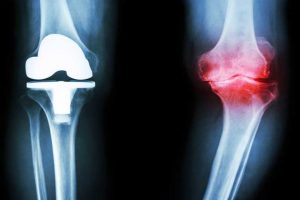

به گزارش کرج رسا، آرتروز زانو امروزه یکی از بیماری‌های بسیار رایج در میان افراد سالمند است. آرتروز مفصل زانو شایعترین بیماری تخریبی از میان مفاصل بدن محسوب می‌شود و احتمال ابتلای زنان به آن بیشتر از مردان است. عوامل زیادی مانند: کهولت سن، مسائل ژنتیکی و وراثتی، نوع شغل، چاقی، عوامل هورمونی و نژادی در بروز این بیماری دخیل هستند. در این بیماری غضروف مفصلی به تدریج شروع به تخریب شدن می‌کند و در نتیجه آن بیمار از درد شدید در زانو‌های خود گلایه دارد. حال دانشمندان موفق شده اند به روشی ساده برای تسکین درد این بیماری دست یابند.

شواهد نشان داد به میزان قابل توجهی از درد این بیماران کاسته شده، اما تصاویر ام آر آی نشان داد مصرف این عصاره تاثیری در ساختار زانو یا بهبودی بیماری نداشته است.